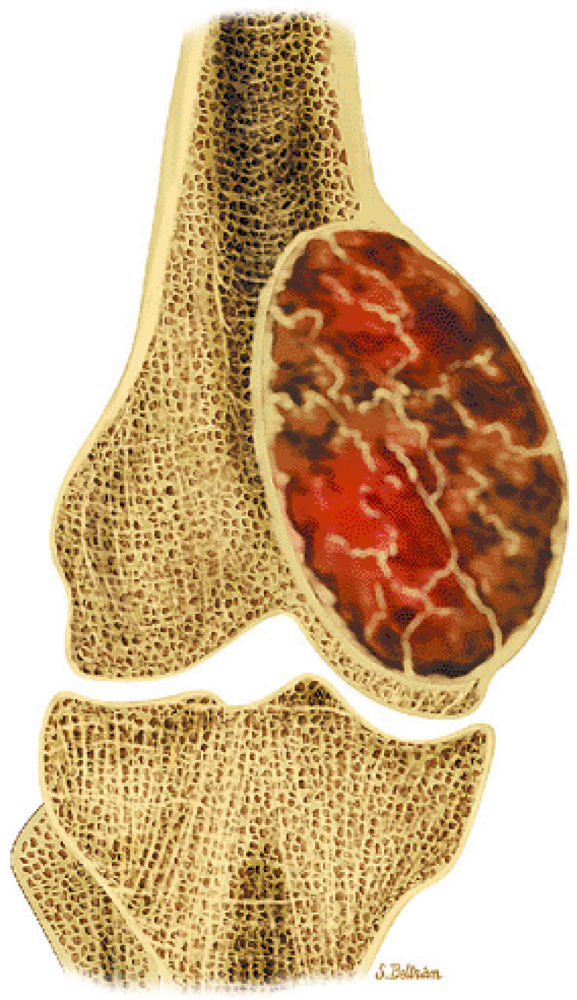

![]() |

FIGURE 14-62 ● Secondary phenomena observed in giant cell tumors.

FIGURE 14-63 ● Giant cell tumor of the distal femur. The tumor extends to the epiphysis.